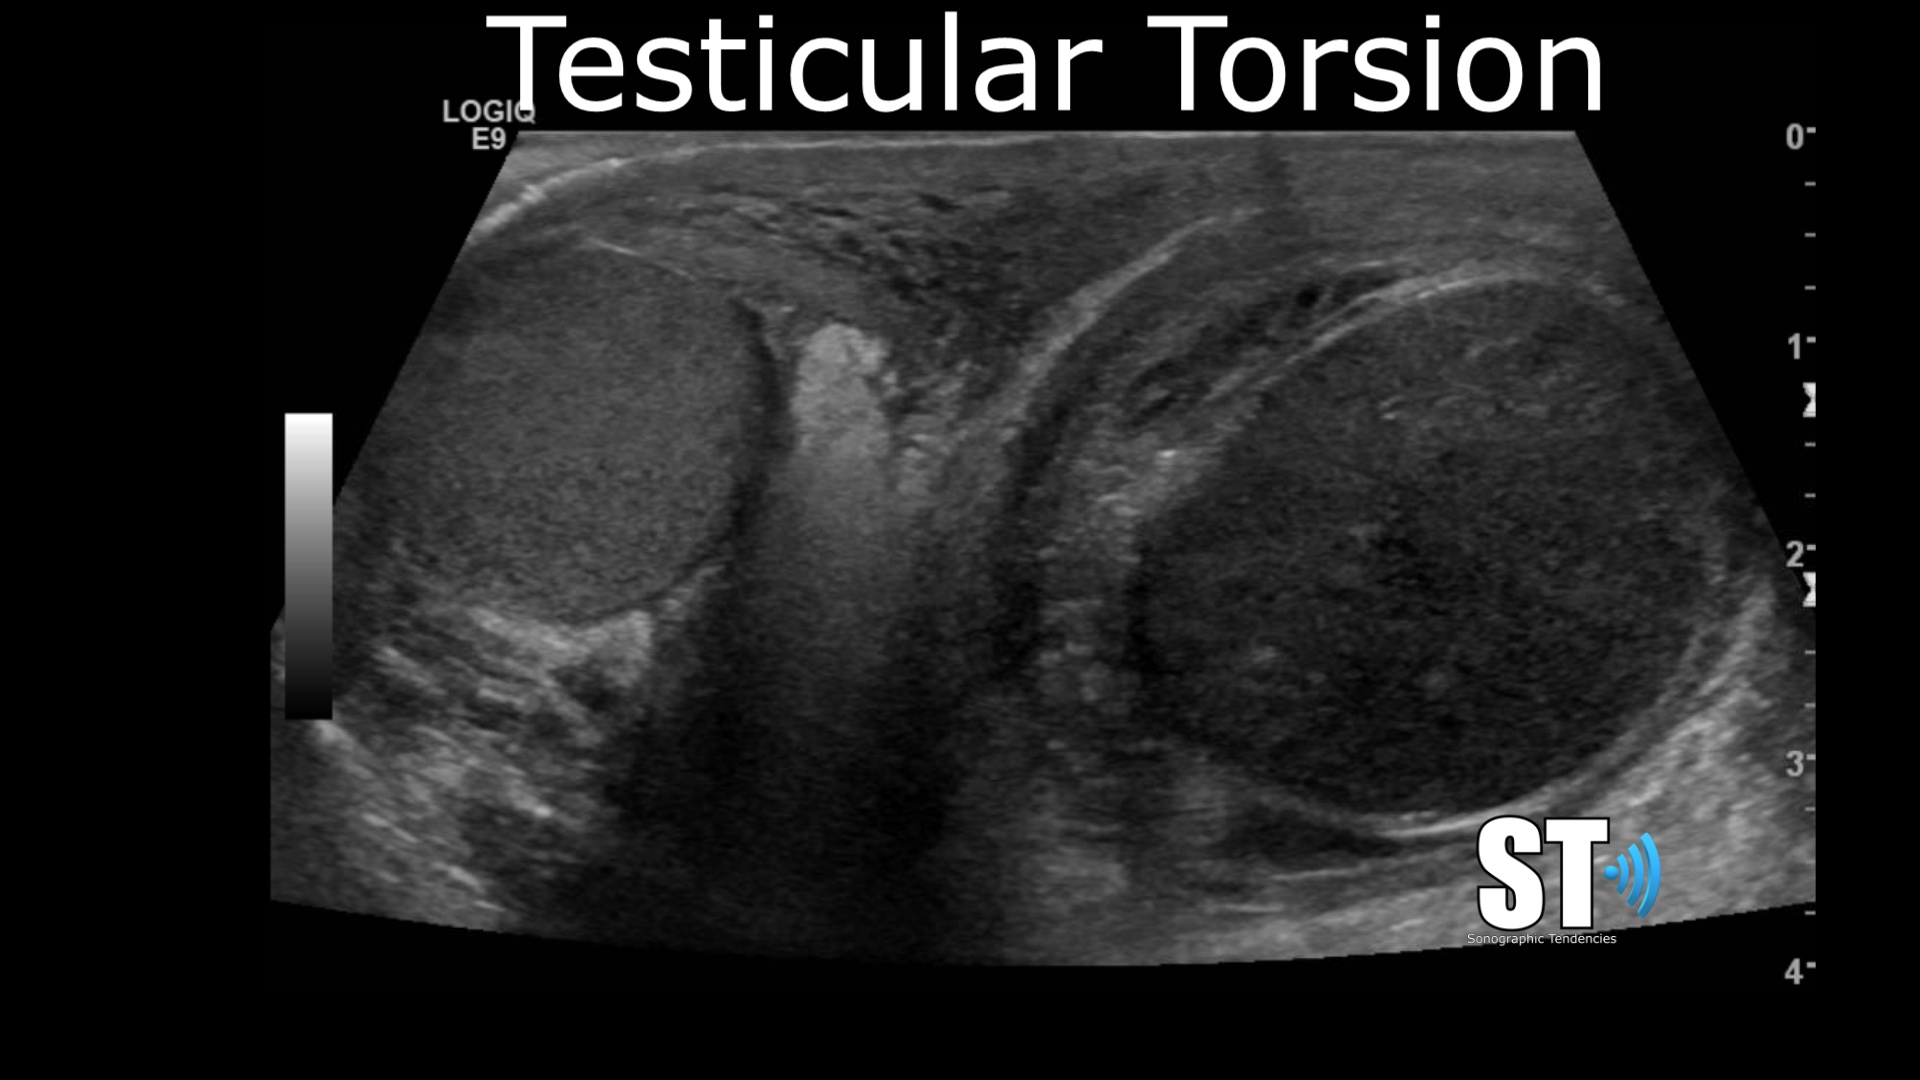

Transverse

Begin in transverse what’s know colloquially as the “twins” view.

This view is great for determining quickly symmetry, position and echotexture. With color doppler you can determine whether there is testicular torsion. In cases of undescended testis you can show a solitary or even empty scrotum if the cryptorchidism is bilateral. Also if there is any testicular lesions they may be apparent form your first image.

Color Doppler

In the same transverse view use color doppler to confirm to see if the blood flow is symmetric. In cases of epididymo-orchitis there will be hyperemia, or increased blood flow to the affected testis. Again if there is testicular torsion it will be apparent.